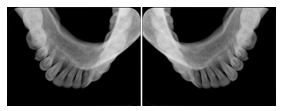

2. A patient requests cosmetic surgery to enhance their facial appearance. The case requires consultation between an orthodontist in New York and an oral surgeon in California. The cephalometric series of 2D projections constructed from a volumetric CT data set that is used for the discussion is arranged by a Structured Display for transfer between the two practitioners.

Cephalometric Series Structured Display

Figure OO-2. Cephalometric Series Structured Display